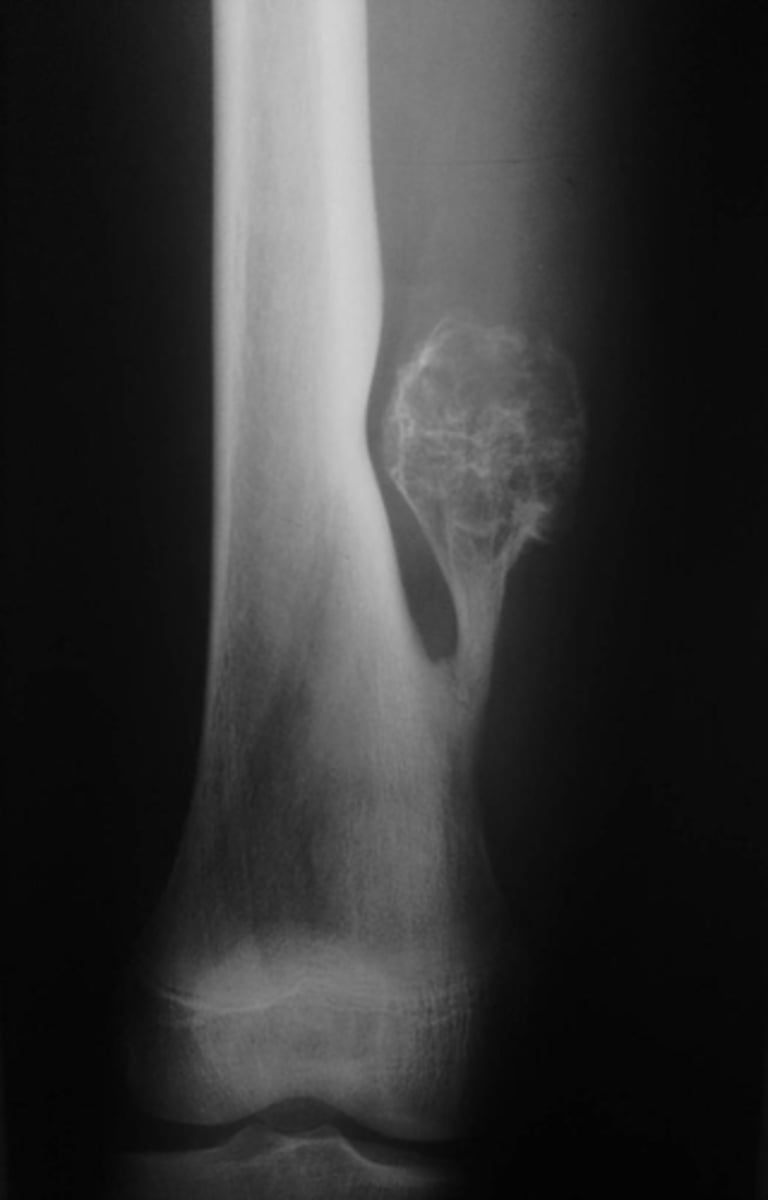

Lateral proximal tibia

Bone

<p>Bone</p>

- Longitudinal: epiphysis/metaphysis (up to joint surface)

- Eccentricity: eccentric

- Transverse: medullary

Location

<p>Location</p>

Monostotic

Mono/polyostotic

<p>Mono/polyostotic</p>

New cards

>1 cm

Size

<p>Size</p>

- Lytic

- Geographic

- Short zone of transition

Behavior

<p>Behavior</p>

- Cortical thinning

- Cortical expansion

Cortex

<p>Cortex</p>

Giant cell tumor

Most likely diagnosis?

<p>Most likely diagnosis?</p>

Refer to orthopedist or oncologist

Next step?

<p>Next step?</p>

Could be aggressive (20%)

Concerns/complications?

<p>Concerns/complications?</p>